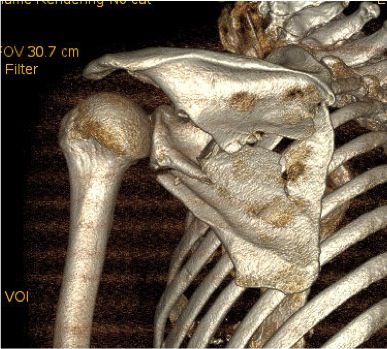

Combined Glenoid and Scapula Fractures

Case 1

- displaced glenoid fracture and neck fracture

- ORIF both through posterior / Judet approach